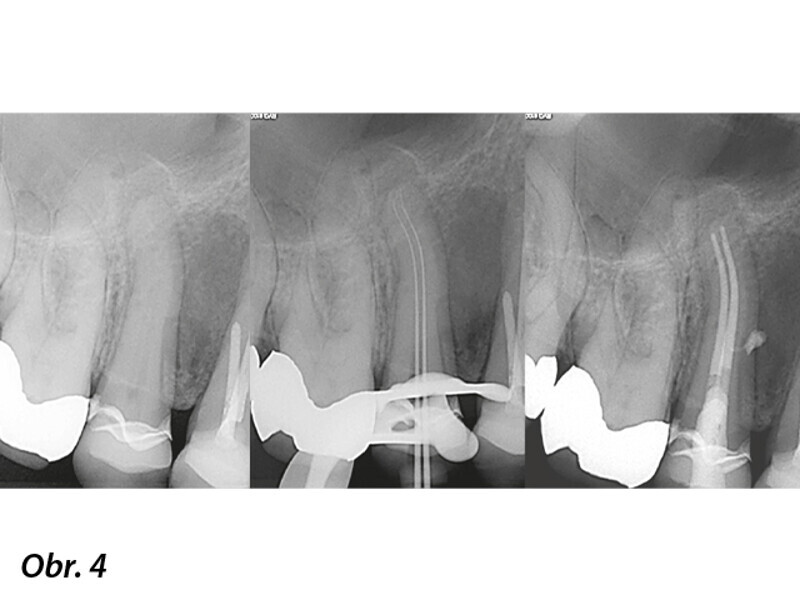

Použití předmíchaných biokeramických materiálů v endodoncii